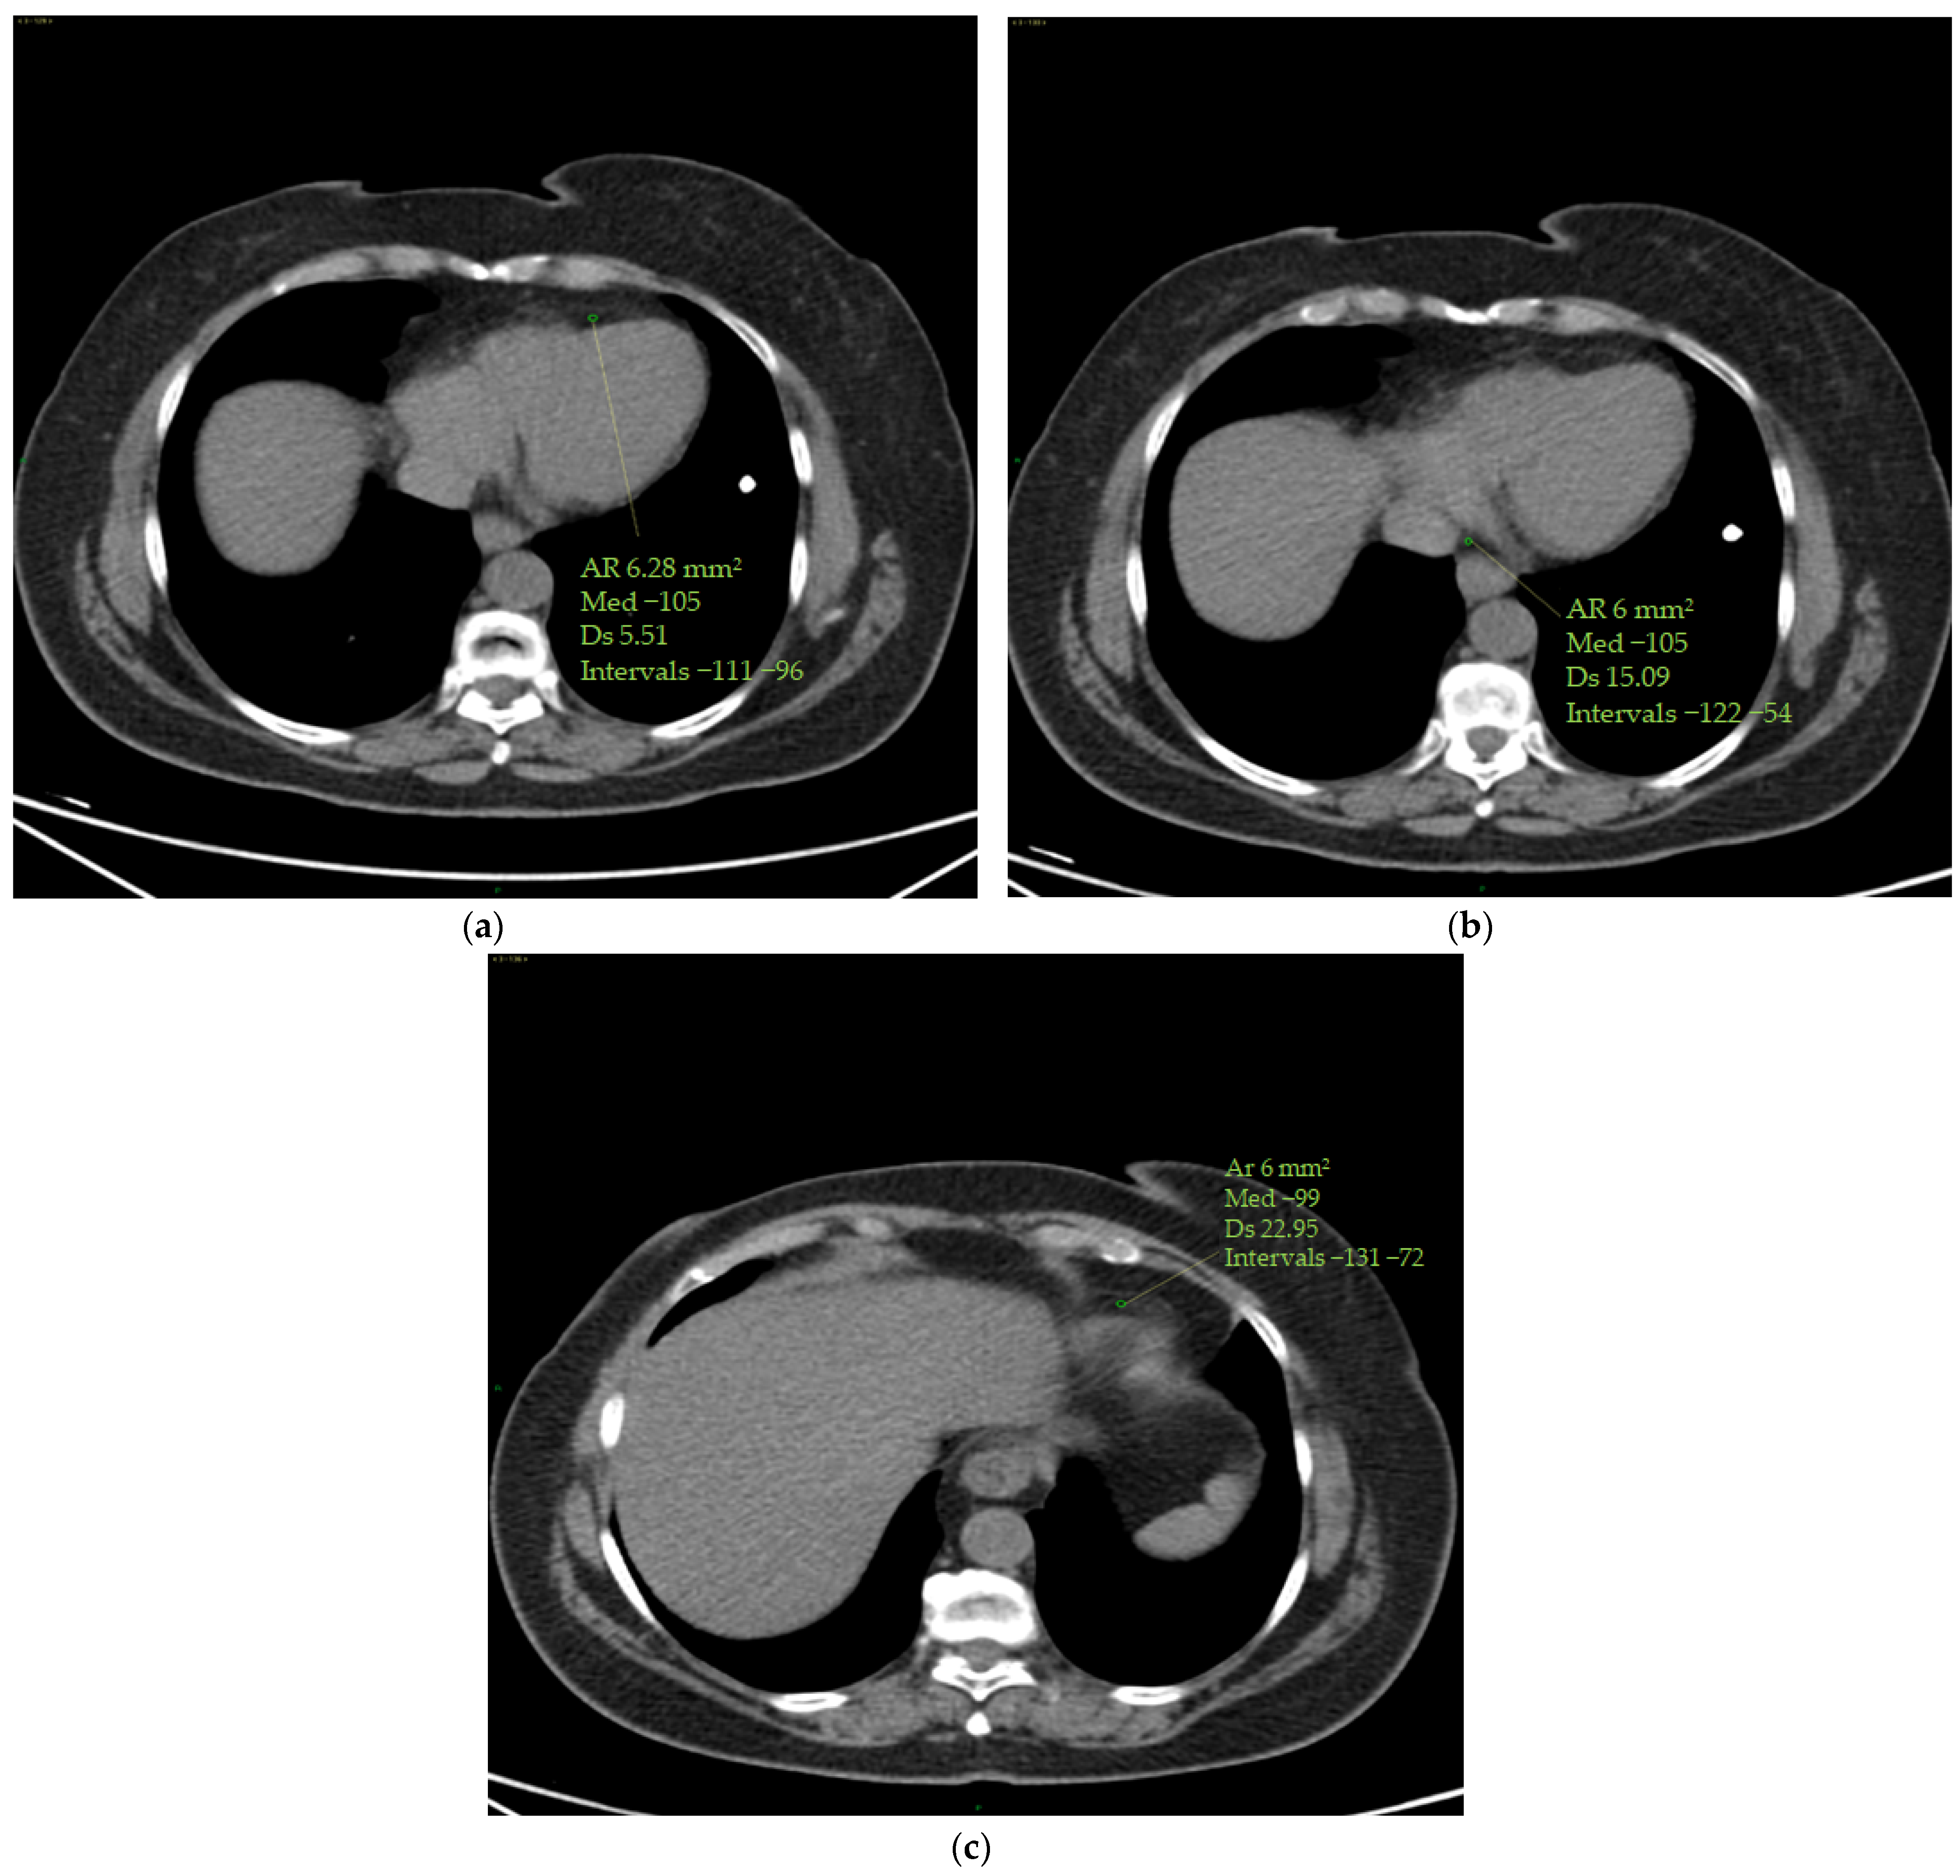

The epicardial adipose tissue (EAT) density was assessed using a specialized workstation (GE Healthcare, General Electric, Boston, MA, USA) at baseline and at the end of therapy. EAT density was measured on basal scans in a 4-chamber projection, at the level of the anterior interventricular sulcus, at the origin of the posterior interventricular artery within the posterior interventricular sulcus and at the level of the cardiac apex (Figure 2).

Figure 2.

(a–c) Epicardial fat density measurement. Using a 4-chamber projection, epicardial fat density was assessed on axial perspective basal CT scans, using a manually placed ROI (with a mean area of 6 mm2) within the anterior interventricular sulcus (a), posterior interventricular sulcus (origin of the posterior interventricular artery) (b) and cardiac apex (c). The figure shows an example of the area of the region of interest (Ar ROI), the mean (med), the standard deviation (Ds) and the range (intervals) of hounsfield units measured.